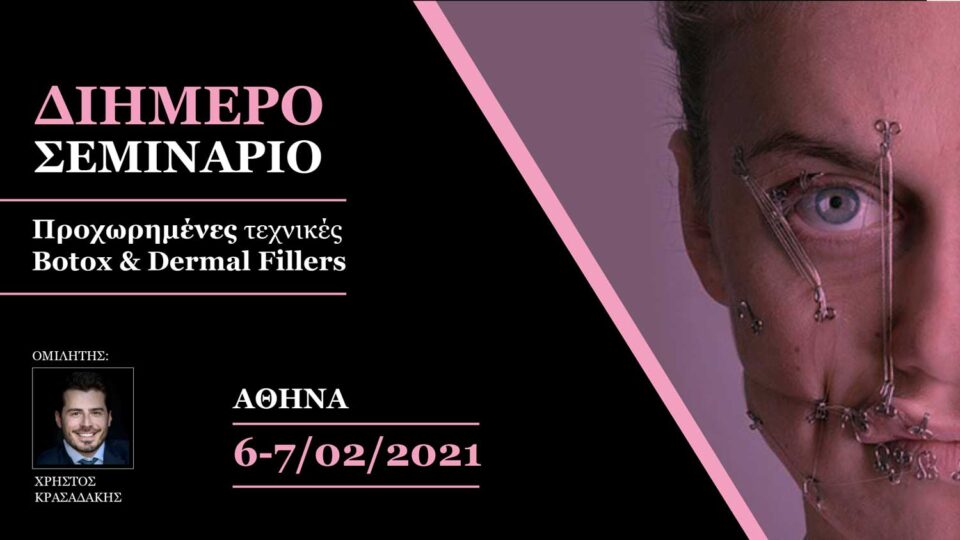

2ήμερο Σεμινάριο – Προχωρημένες τεχνικές Botox – Fillers (Αθήνα)

€1,450.00

Ημερομηνία διεξαγωγής: 6-7/02/2021 (Αθήνα)

SOLD OUT!

Σεμινάρια (Αρχείο)